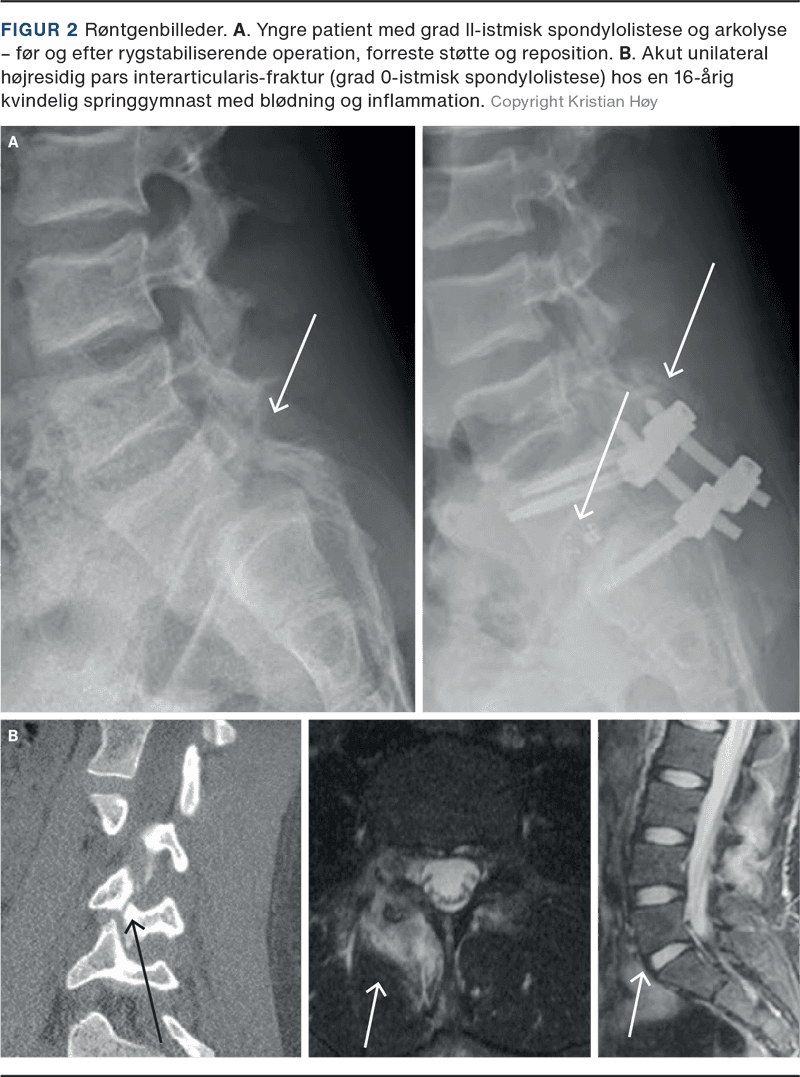

DSL forekommer primært hos ældre over 50 år, og der er en overhyppighed af kvinder [6]. Degeneration af discus medfører instabilitet i facetleddet, hvilket leder til fremadskridning af den kranielle hvirvel – hyppigst ved L4-L5, men tilstanden kan ses i alle degenererede led [7]. Den øgede instabilitet medfører progression i de degenerative forandringer med osteofytformation, ligamenthypertrofi og facetledsartrose i det instabile led, hvilket kan give foraminal- og spinalstenose [8] (Figur 3). Progression af Meyerding ved DSL er således en følge af gradvis discusdegeneration. DSL forekommer i 75% af tilfældene som grad I [8] og leder sjældent til sværere afglidning end grad II, da facetleddene holder hvirvlen på plads i modsætning til ved ISL [9]. I The Copenhagen Osteoartitis Study med 4.151 patienter (heraf 70% kvinder med en gennemsnitsalder på 65 år; gennemsnitsalderen hos mændene var 62 år) forekom DSL med en prævalens på 8,4% hos kvinderne og 2,7% hos mændene. Der er således en høj prævalens og en skæv kønsratio i Danmark. Desuden viste studiet, at BMI, alder og lumbal hyperlordose var risikofaktorer for DSL hos kvinder, mens kun alder var risikofaktor hos mænd [10].